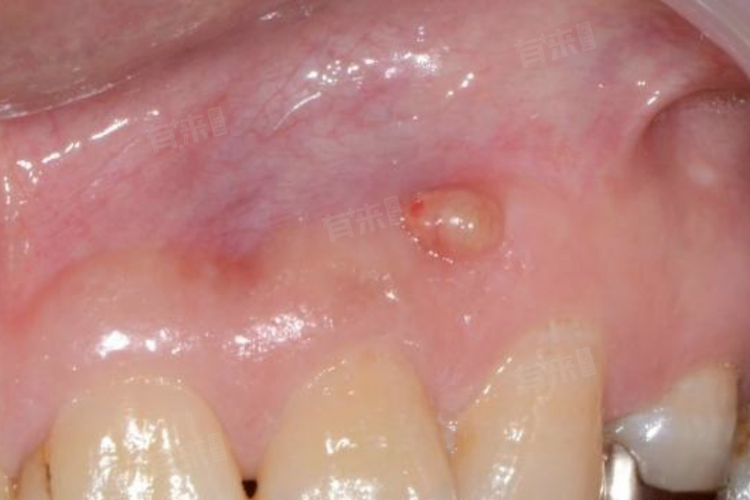

牙龈上长出脓包是一种较为常见的口腔问题,考虑是根尖周炎、牙周炎、智齿冠周炎,以及口腔黏膜损伤感染、全身性疾病等。

1、根尖周炎:这是导致牙龈脓包最常见的原因之一。当牙齿由于龋齿、外伤等原因导致牙髓感染后,炎症会逐渐扩散到根尖部位。如果炎症没有得到及时治疗,就会在根尖周围形成脓肿,脓液无法排出时,就会在牙龈上形成脓包。这个脓包通常会有疼痛、肿胀的感觉,尤其是在咬合时疼痛可能会加重。

2、牙周炎:严重的牙周炎也可能引起牙龈脓包,牙周炎会导致牙周组织发炎、破坏,当炎症发展到一定程度时,细菌可以通过牙周袋进入牙龈组织内部,形成脓肿。这种脓包一般伴随着牙龈出血、牙齿松动等症状,对口腔健康造成很大威胁。

4、口腔黏膜损伤感染:口腔黏膜受到外力损伤,如咬伤、烫伤等,若没有及时处理,伤口容易被细菌感染,进而引发炎症,形成脓包。这种脓包通常出现在受伤部位的牙龈上,周围组织可能会红肿、疼痛。